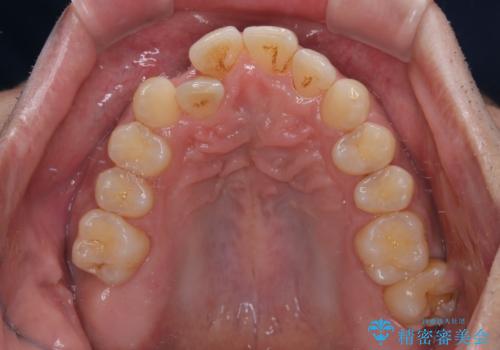

- 上下前歯のデコボコを気にして来院された患者様です。

上顎前歯の舌側転位が顕著であったため、治療期間が長くなると思われましたが、僅か1年で無事に終えることができました。